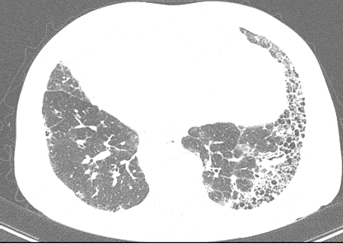

결정형 실리카 분진은 폐 속에서 녹지 않는다.

미세한 규사 가루가 폐포 깊숙이 들어가 조직을 지속적으로 손상시키고 염증을 일으키며, 결국엔 아래와 같은 질병으로 이어진다.

- 규폐증(Silicosis)

- 폐섬유화증

- 폐기능 저하

- 폐암